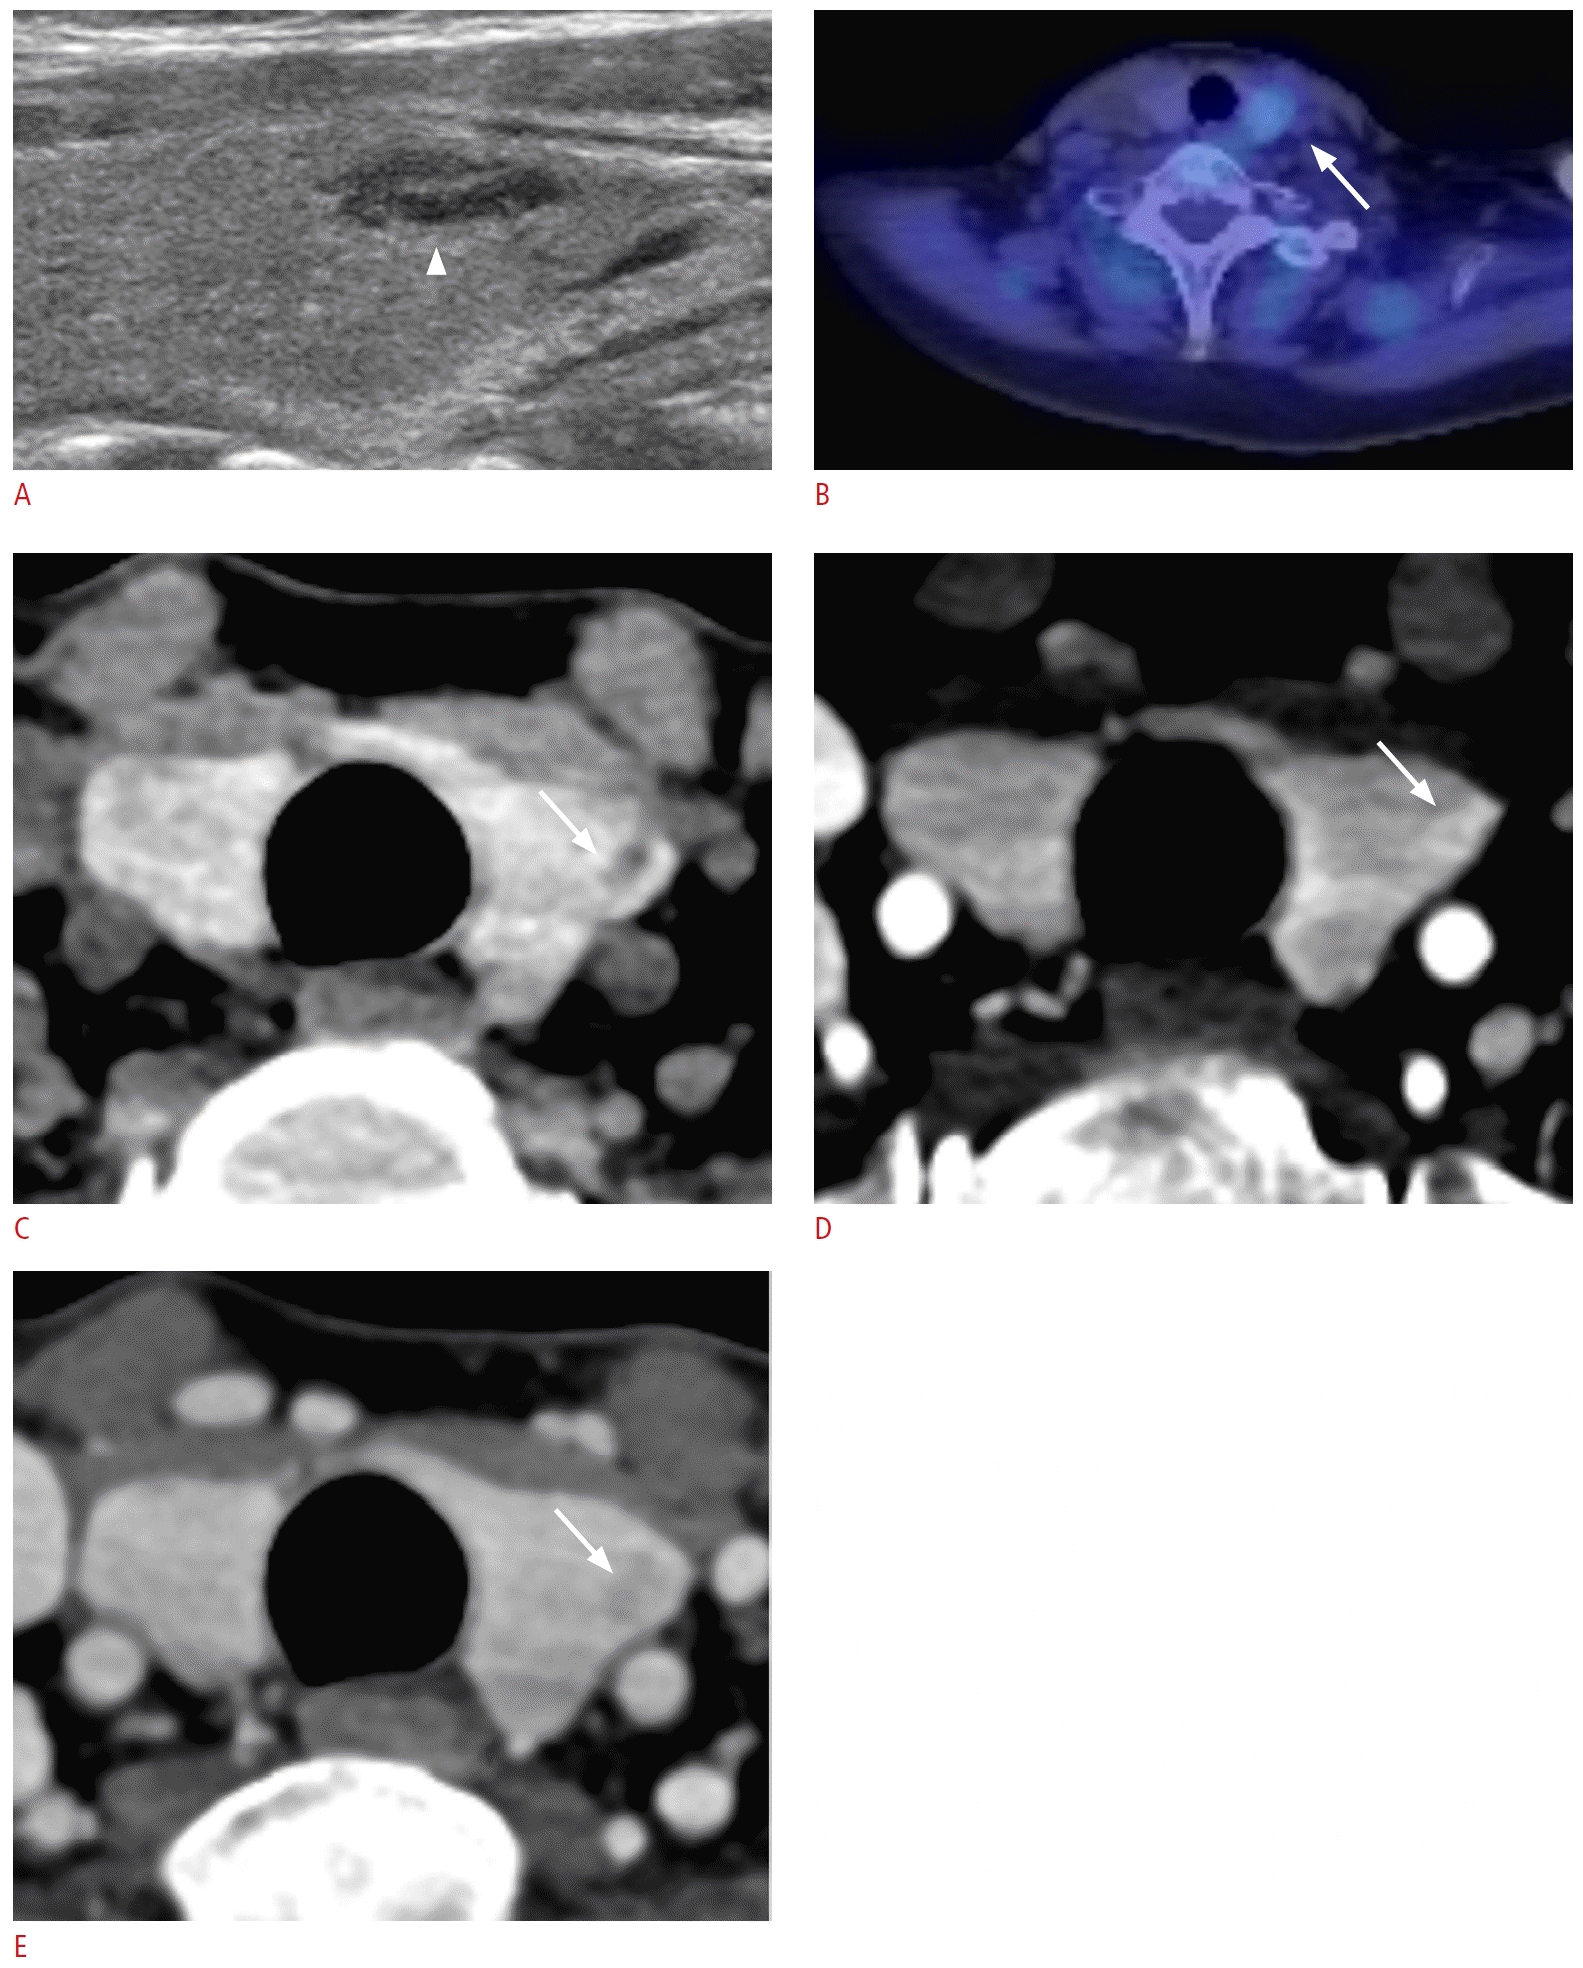

72. Cuderman A, Senica K, Rep S, Hocevar M, Kocjan T, Sever MJ, et al. (18)F-Fluorocholine PET/CT in primary hyperparathyroidism: superior diagnostic performance to conventional scintigraphic imaging for localization of hyperfunctioning parathyroid glands. J Nucl Med. 2020; 61:577–583.

73. Giovanella L, Bacigalupo L, Treglia G, Piccardo A. Will (18) F-fluorocholine PET/CT replace other methods of preoperative parathyroid imaging? Endocrine. 2021; 71:285–297.

74. Kim SJ, Lee SW, Jeong SY, Pak K, Kim K. Diagnostic performance of F-18 fluorocholine PET/CT for parathyroid localization in hyperparathyroidism: a systematic review and meta-analysis. Horm Cancer. 2018; 9:440–447.

77. Piccardo A, Trimboli P, Rutigliani M, Puntoni M, Foppiani L, Bacigalupo L, et al. Additional value of integrated (18) F-choline PET/4D contrast-enhanced CT in the localization of hyperfunctioning parathyroid glands and correlation with molecular profile. Eur J Nucl Med Mol Imaging. 2019; 46:766–775.

80. Michaud L, Balogova S, Burgess A, Ohnona J, Huchet V, Kerrou K, et al. A pilot comparison of 18F-fluorocholine PET/CT, ultrasonography and 123I/99mTc-sestaMIBI dual-phase dual-isotope scintigraphy in the preoperative localization of hyperfunctioning parathyroid glands in primary or secondary hyperparathyroidism: influence of thyroid anomalies. Medicine (Baltimore). 2015; 94:e1701.